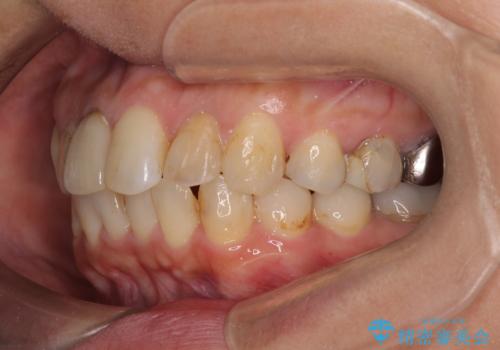

【モニター】処置歯の多い歯列 インビザラインでデコボコを整える

- 上下前歯のデコボコを気にして来院された患者様です。

歯列としては、ワイヤー装置でもインビザラインでも、どちらでも対応可能でしたが、処置されている歯が多く、ワイヤー装置を装着するためには処置歯のやり直しが必要な状態でした。

インビザラインでもアタッチメントを装着できないという同様のデメリットがありますが、比較的矯正治療を行いやすい歯列であったので、インビザラインによる矯正治療を行うこととしました。

術中や仕上がりに特に大きなトラブルはなく、スムーズに治療を終えることができました。